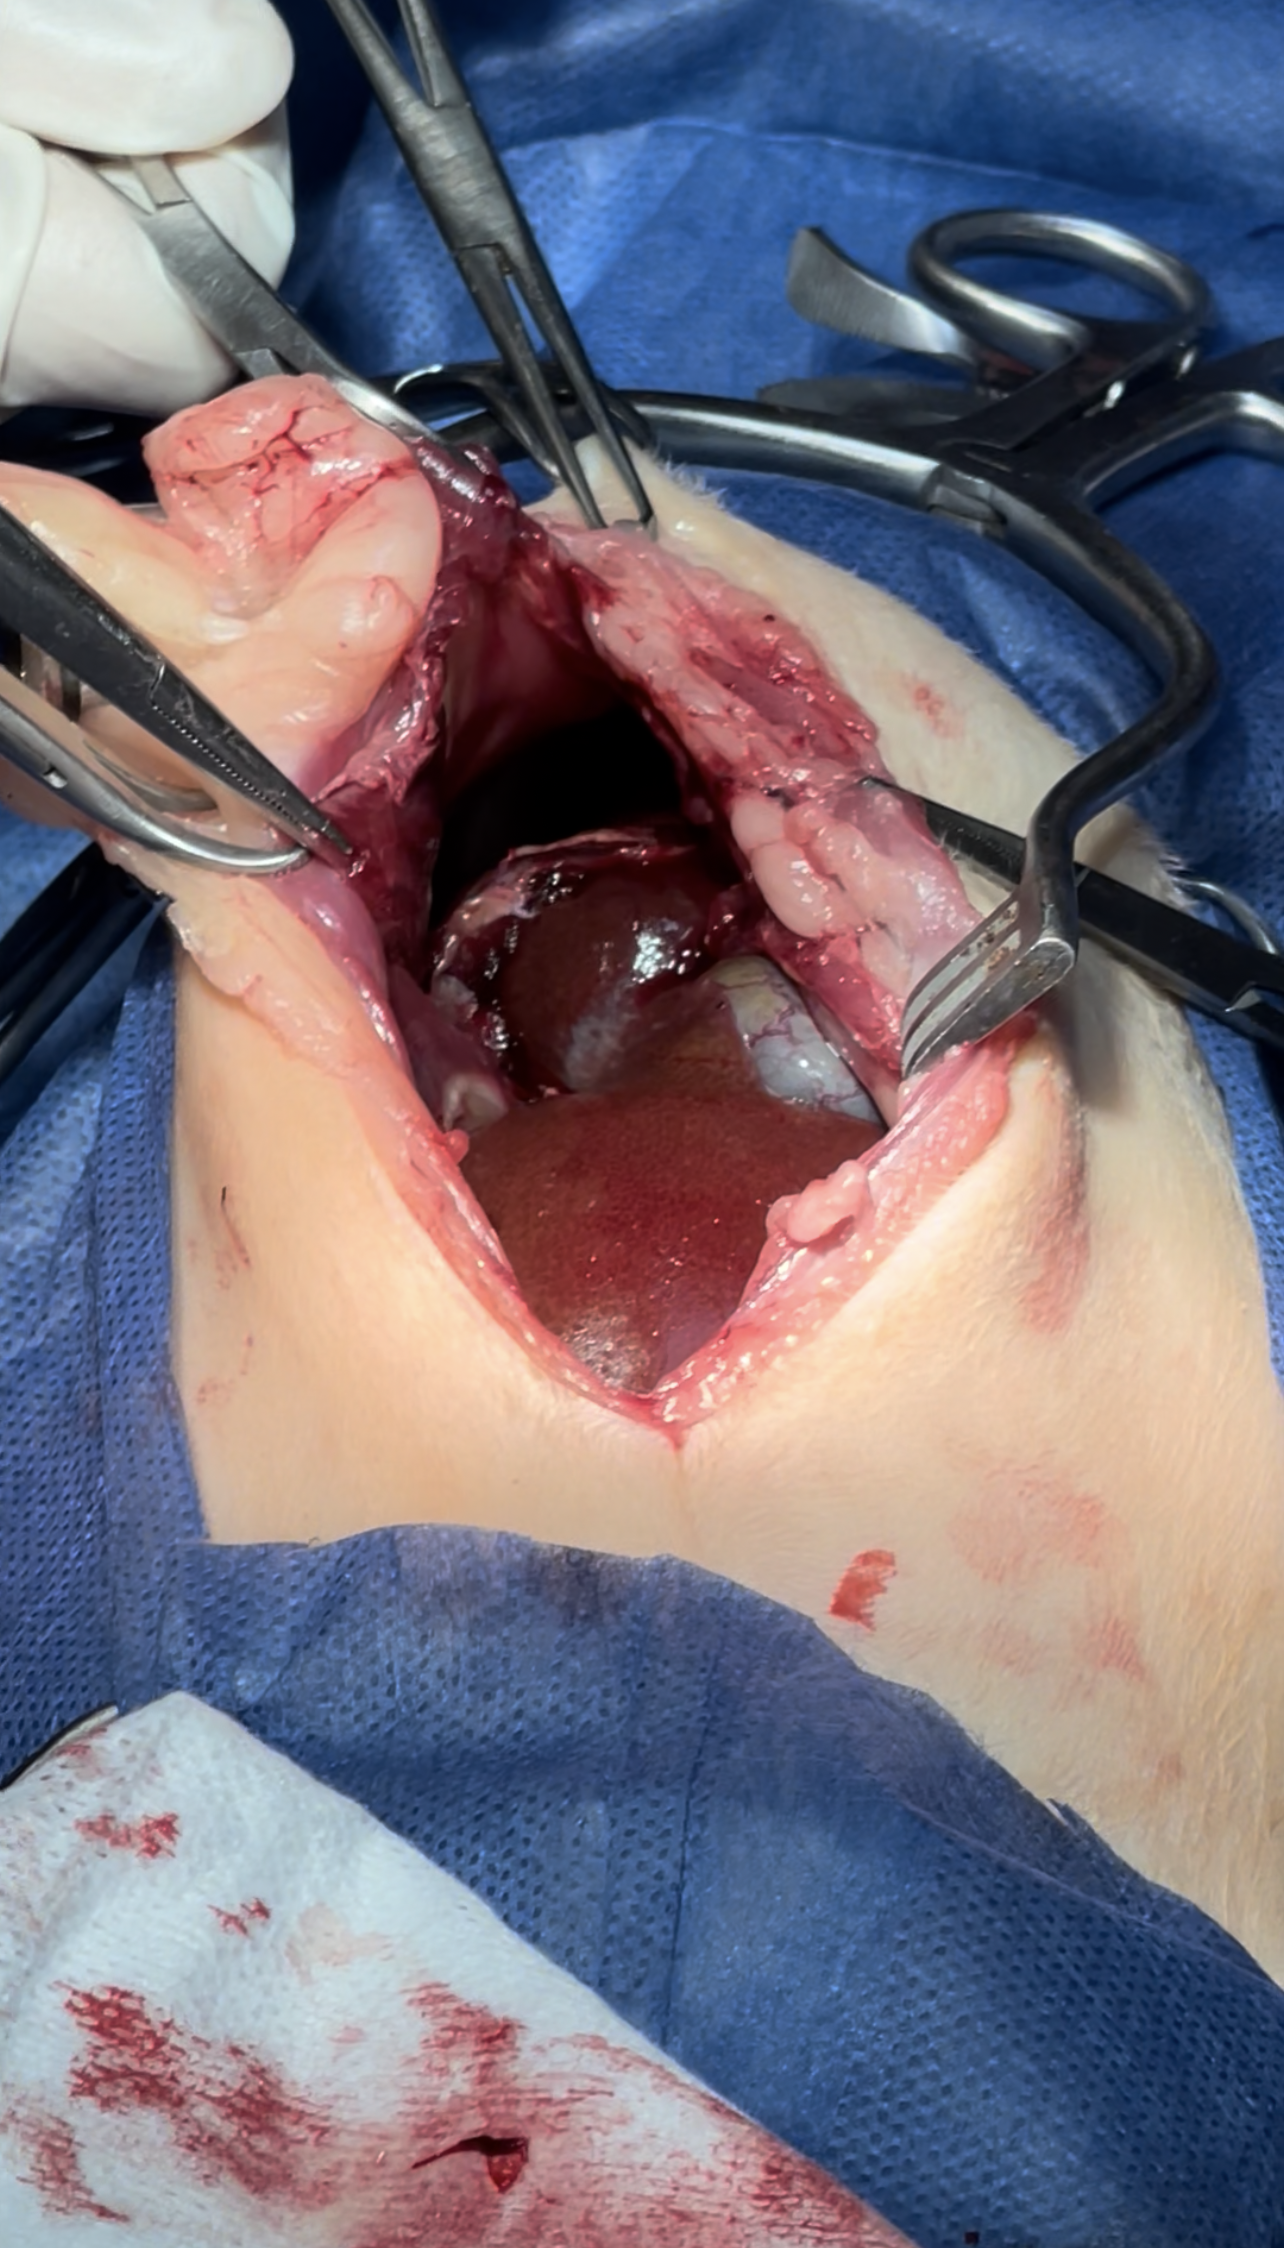

intestines & Liver lobe passing through a narrow hole after being healed over

Dissection of the intraabdominal adhesive part of the live

Widening the herniation to allow organ exteriorization